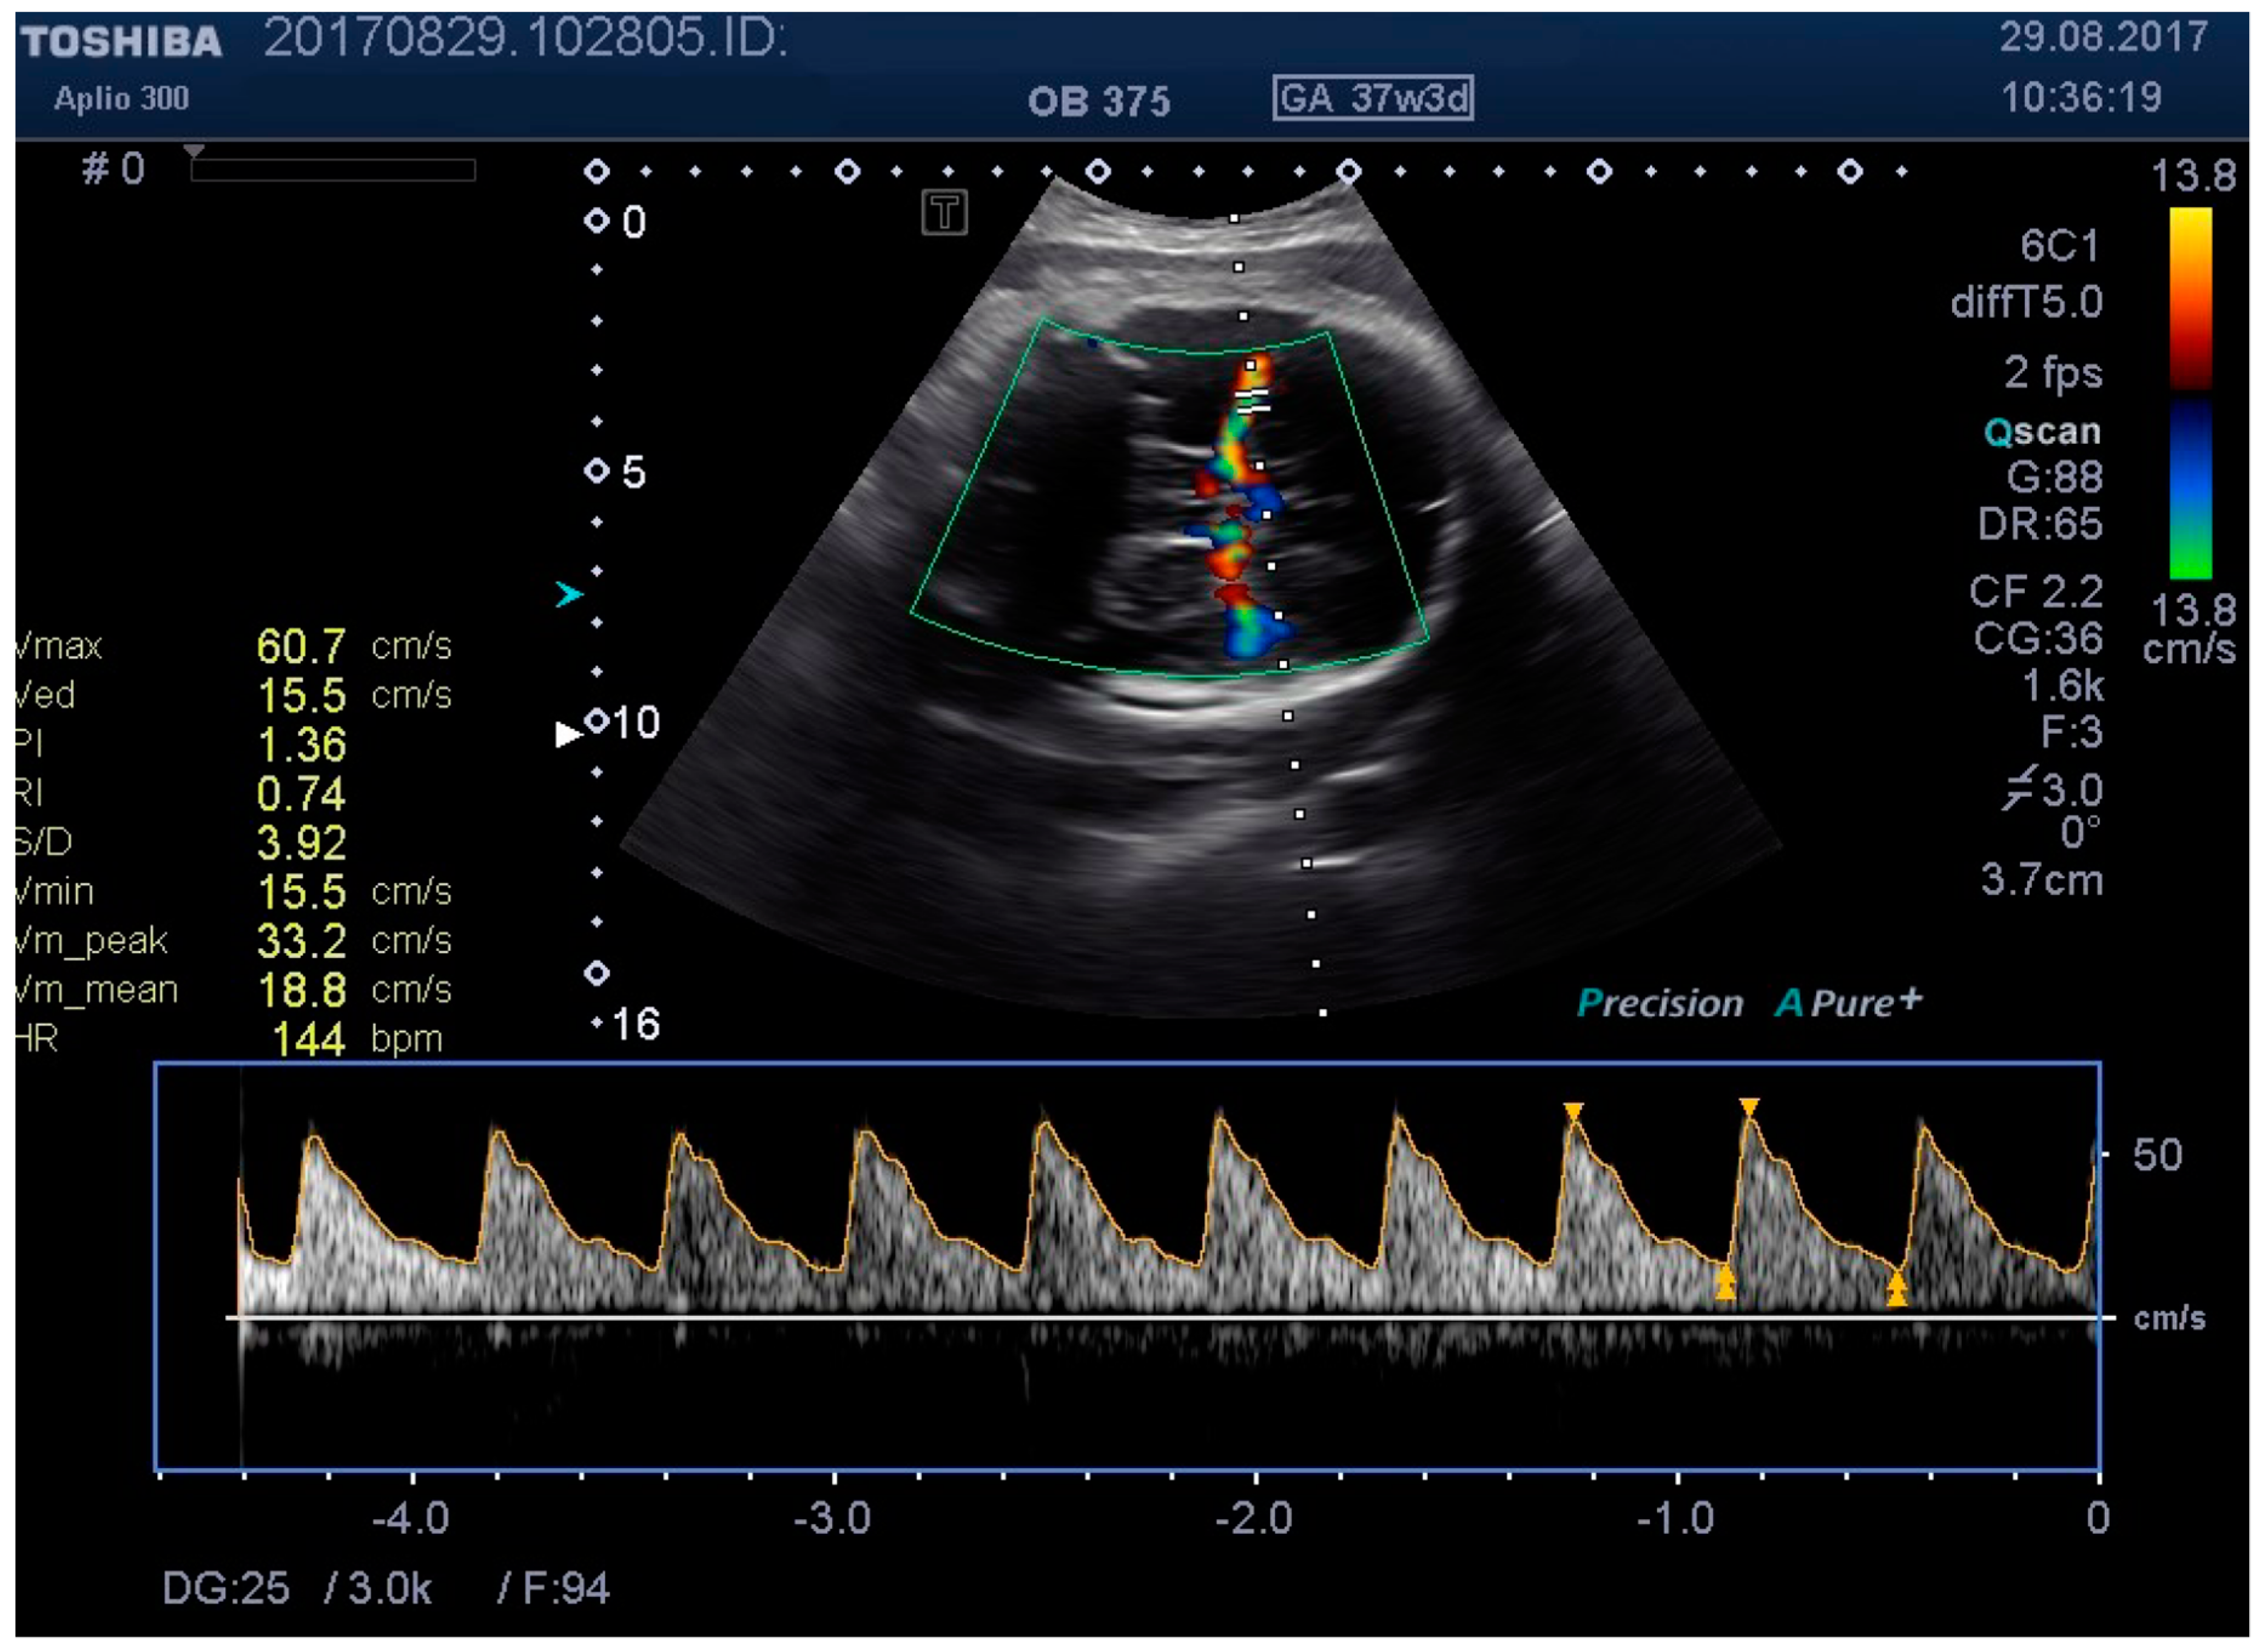

Figure 5. MCA Doppler spectrum with baseline pressure.

Medicina 55 00410 g005

We examined the patients by transabdominal US, evaluating fetal lie and presentation, amniotic fluid index (AFI), area of placental insertion, and the abdominal wall thickness (AWT) including skin, subcutaneous tissue, and muscular wall. As a second step, we have evaluated the fetal cerebral vascularization, referring to the circle of Willis, with the help of color Doppler US, demonstrating the fetal MCA and recording the distance between the probe and the targeted vessel (e.g., MCA). By using pulsed Doppler examination, we recorded the flow velocity waveforms in the MCA, and measured the RI, PI, and PSV (using the highest point of the waveform). At the same time, we recorded, in a blinded manner, the applied pressure on to the maternal abdominal wall, considering this as a baseline pressure—needed for a proper evaluation of MCA. We then repeated the same measurements at two different higher pressure levels, while at the same time having a proper image of the targeted vessel. For the study methodology, we noted these pressure levels as level 2 and level 3.

Figure 1, Figure 2, Figure 3, Figure 4, Figure 5, Figure 6 and Figure 7 and Table 3 show the differences between MCA RI, PI, and PSV measured in the studied group, applying three different levels of abdominal pressure. As shown in the subsequent tables and figures, there are significant differences for the PI and RI levels with increase in abdominal pressure (median PI 1.46, 1.58, and 1.92, respectively; median RI 0.74, 0.78, and 0.85, respectively). Data are not following the normal distribution, thus, we used a Kruskal–Wallis test, which confirmed p < 0.05, for both PI and RI. At the same time, we found no significant differences for PSV in the studied group in relation to the increase in abdominal pressure (median PSV 39.56, 40.10, and 39.70 respectively). Data are not following the normal distribution, thus, we used a Kruskal–Wallis test, which showed p > 0.05.